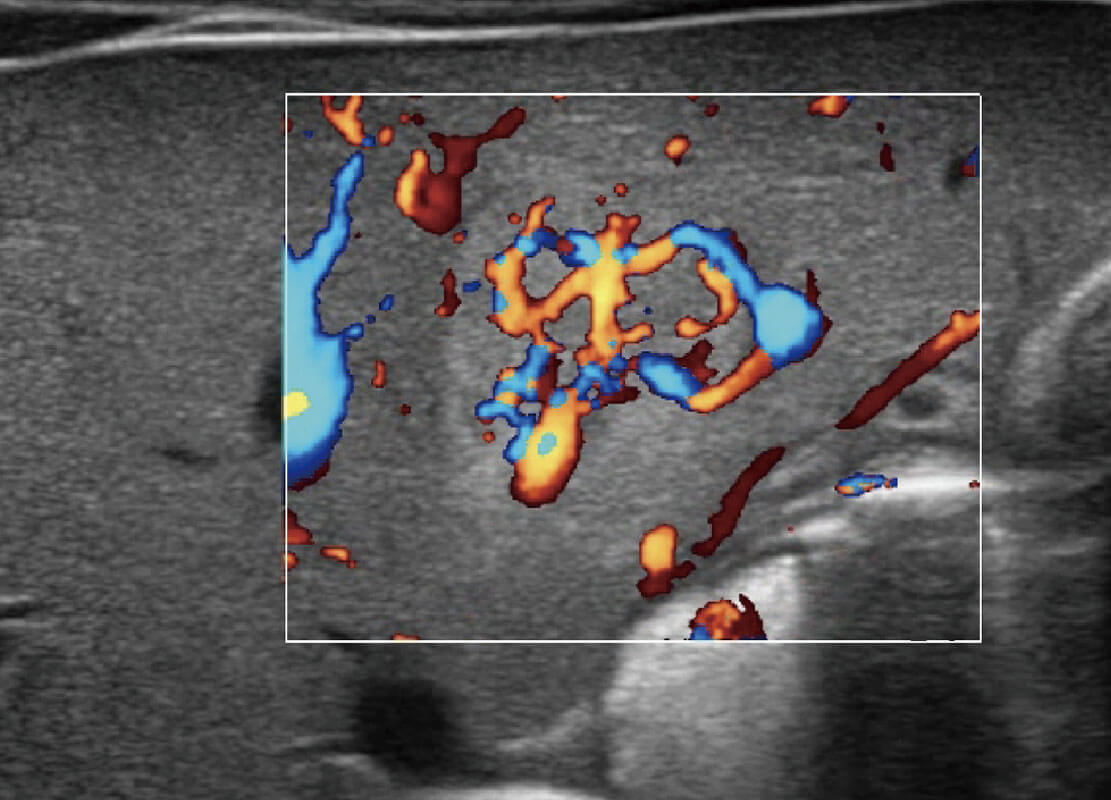

P60优异的图像质量搭载专科探头,在妇科基础疾病的诊断、卵泡生长的监测、输卵管通畅情况的判别等方面为您提供生殖应用方案。

胎儿体循环

四腔心血流